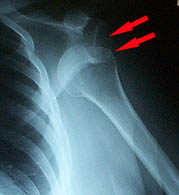

SHOULDER DISLOCATION X-RAYS

Dislocated